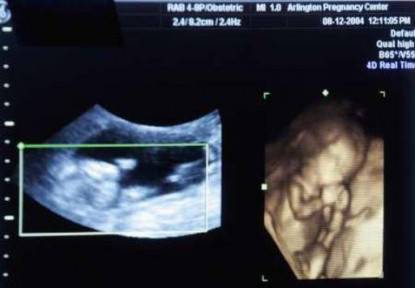

Kantabai Gunvant Thakre, la sessantenne donna di origine indiana protagonista di questa incredibile storia, aveva cominciato a lamentare dei dolori allo stomaco da circa 2 mesi e, successivamente, gli ultrasuoni avevano rivelato una massa che sembrava cancerogena.

L’ecografia però ha stabilito che non si trattava di un tumore, ma di una massa calcificata. Grazie alla risonanza magnetica sono emersi anche organi appartenenti a questo corpo estraneo.

La dottoressa Murtaza Akhtar, a capo del reparto di chirurgia del Lata Mangeshkar Hospital, ha commentato: “è stato dopo che la donna è stata sottoposta a una risonanza magnetica che i medici hanno potuto constatare che si trattava dello scheletro di un bambino”.

In seguito i dottori sono venuti a sapere che la donna, a 24 anni, aveva avuto una gravidanza ectopica, il che voleva dire che il feto non si era sviluppato nell’utero, ma in un’altra parte del corpo.

Nel caso della donna indiana un team di medici ha eseguito una delicata operazione per rimuovere il feto calcificato che si era stabilito tra l’intestino, la vescica e l’utero.

Alla fine è stato rinvenuto un feto completo di tutte le ossa.